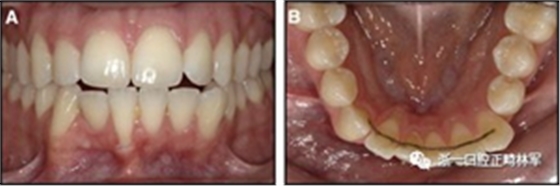

一顆或兩顆尖牙位置的橫向變化可能發(fā)生在與每顆牙齒粘合的小弓絲上,并且在極軟弓絲(圖3)和柔性螺旋弓絲(圖4)上都可以看到。較大直徑的弓絲會產(chǎn)生不同類型的橫向變化。較硬的弓絲與更小的弓絲相比,在尖牙之間產(chǎn)生更多的相關(guān)關(guān)系。弓絲的扭曲會導(dǎo)致尖牙的往復(fù)運動和弓形的歪斜(圖5)。相對較硬弓絲的向下偏斜可以通過尖牙產(chǎn)生擴(kuò)張(圖6)。

圖3.極軟弓絲完全完好,在多個空間平面上的拱形歪斜,右側(cè)尖牙的面部傾斜以及右側(cè)側(cè)切牙和中切牙在相反方向上的扭矩:A,頰面視圖; B,咬合面視圖。